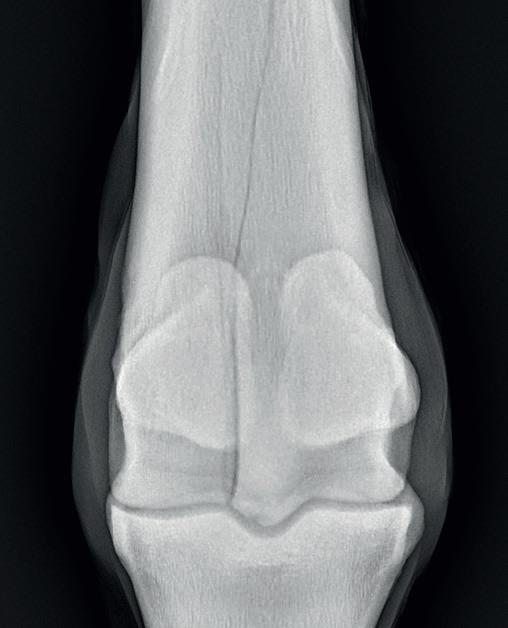

Bone

Bone has many important roles that involve locomotion, the storage of minerals (especially calcium and phosphate), soft tissue and vital organ protection, and the support and containment of bone marrow. Bone is a specialised connective tissue, and together with cartilage forms the strong and rigid endoskeleton. The bone is continuously altering through two processes called bone modelling and bone remodelling, involving four cells referred to as osteoclasts, osteoblasts, osteocytes and bone lining cells.

Osteoblasts secrete bone matrix in the form of non-mineralised osteoid, which is then mineralised over a few weeks to form a bone matrix. Osteoclasts are involved in resorption of bone as this process occurs faster than the formation of bone. When the bone surfaces are not in the development or resorption phase, the bone surface is completely lined by a layer of flattened and elongated cells termed bone-lining cells. Osteocytes are derived from osteoblasts and are highly specialised to maintain the bone matrix. They are designed to survive hypoxic conditions and maintain biomineralisation of the bone matrix. Osteocytes also control osteoblastic and osteoclastic activities allowing bone remodelling.

The function of bone modelling is to alter and maintain shape during growth. As the horse grows and develops, bone modelling occurs with the acquisition and removal of bone. While the young horse grows and develops, bone modelling allows the bone to endure strains from everyday work and exercise. The adult skeleton undergoes a minimal amount of bone modelling. Due to the presence of the high frequency of bone modelling in young horses, their skeletal strength is highly influenced by strains to their bones during exercise and daily use. With this knowledge, it has been concluded and confirmed that

short-term dynamic exercise of an adolescent can lead to beneficial changes to its bone morphology.

Bone remodelling is a different process, in which old and damaged bone is renewed, which enables the bone to respond and adapt to changing functional situations. Bone remodelling is usually a coordinated relationship between bone resorption and bone formation. This process occurs throughout the horse’s life with the renewal of primary, damaged or old bone. Osteoclasts absorb old and damaged bone, and the osteoblasts form new bone and lay down new bone matrix until the earlier absorbed bone is replaced. In those animals with musculoskeletal disease or damage, there is an imbalance of osteoblast and osteoclast activity. With the knowledge that osteoblast activity to make new bone takes months whilst osteoclast activity of removing old and damaged bone only takes a few days to two weeks, bone that is being repaired is at a high risk of further injury as bone removed has not been completely replaced. Multiple studies have shown that exercise while growing can provide lifelong benefits; however, it must be done with care and knowledge.

In addition, many studies have shown that exercise of a dynamic nature in moderate distances, such as that achieved in the pasture or prescribed short-distance high-speed work is beneficial to musculoskeletal development and may prevent injuries when entering race training. It has also been observed that long slow work does not increase bone strength. Below is a summary of the young horse response of the various types of exercise.

TYPE OF EXERCISE RESPONSE OF BONE

Pasture access

Trotting

Sprinting

• Increased mineral content of bone

• Greater cannon bone circumference

• Greater deposit of bone minerals when carrying weight compared to no weight

• Greater bone strength

• Greater bone mineralisation

• Greater altered bone shape

Treadmill

Endurance training

• Greater bone density

• Greater impact strength on cannon bone

• No change in bone density